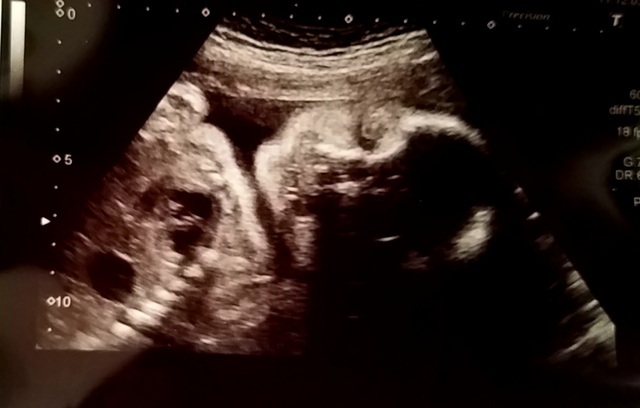

29週2日(29w2d・男の子)|ハニコロ さん(36歳)

エコー写真撮影時のエピソード:

ここ最近とても胎動を感じる日々。

足を伸ばしている様な寝返りをうっている様な(^^)しゃっくりも感じだしてきました。

妊娠後期になり少し屈むのも足の負担になったり、食べた後にムカムカしたり… でも胎動を感じた時には幸せが溢れる日々です。